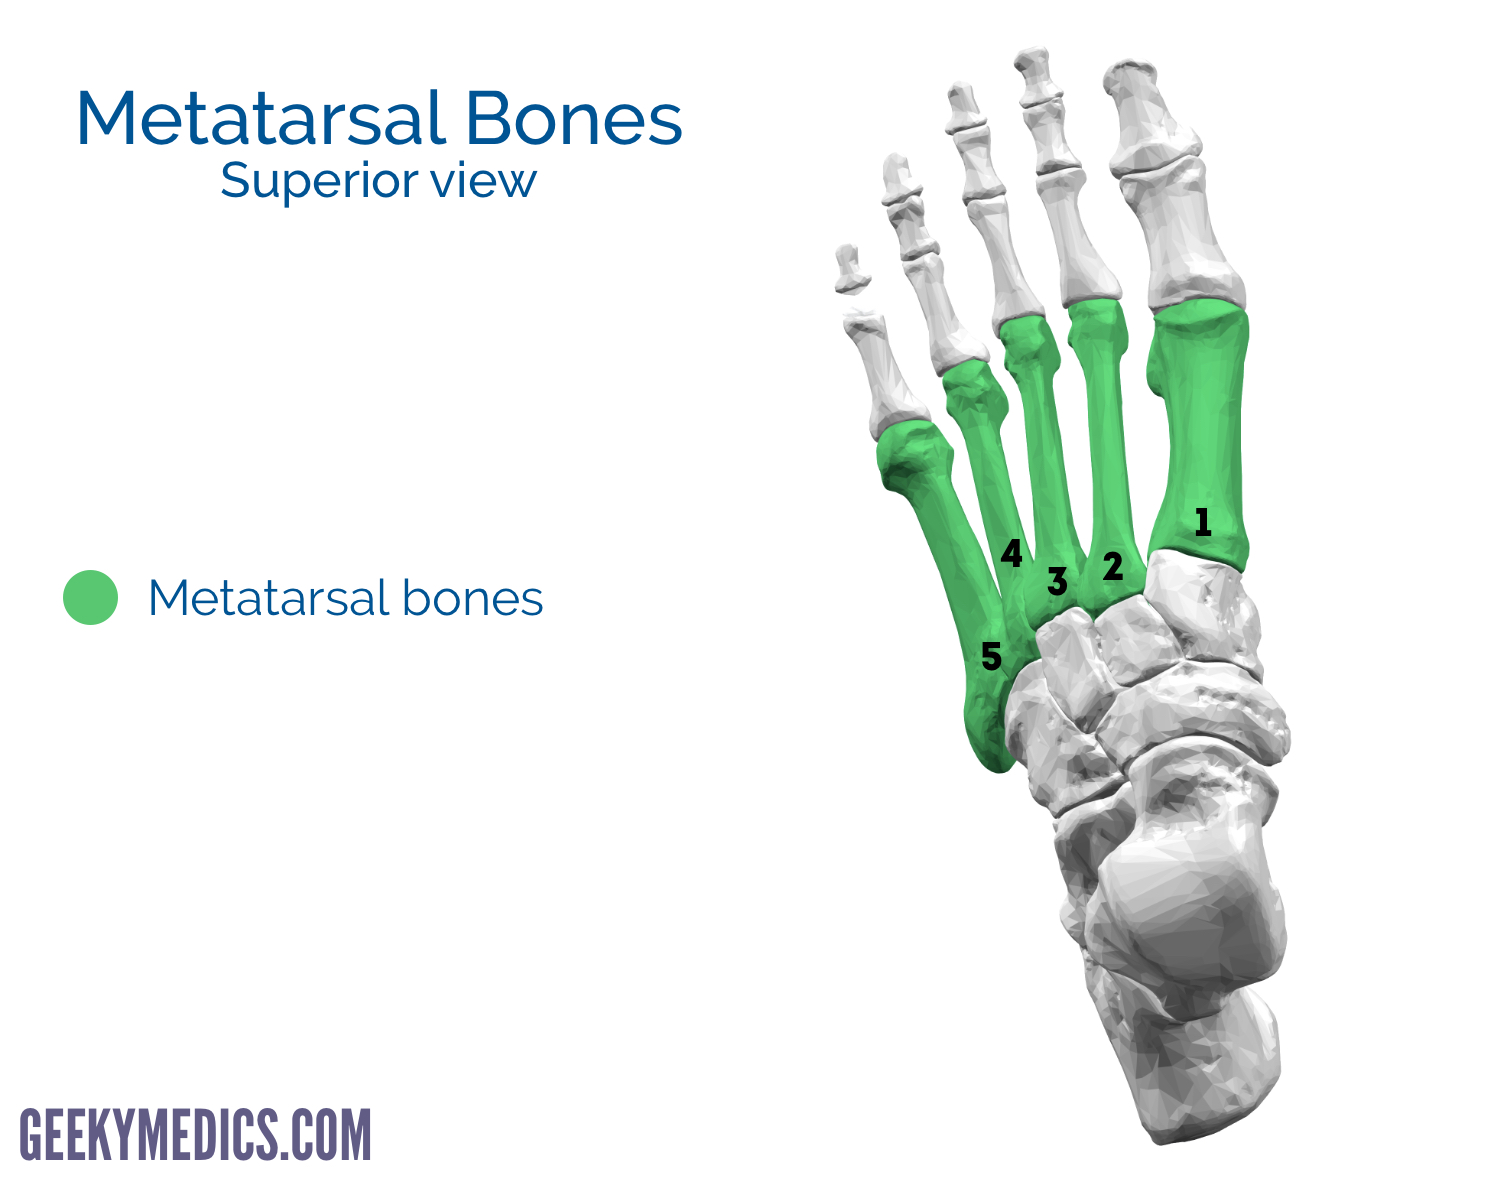

what are the bones of the foot?

metatarsals

what do the metatarsals look like?

what are the landmarks of the metatarsals?

base

shaft

head

what is the styloid process of the 5th metatarsal?

insertion site for peroneus brevis